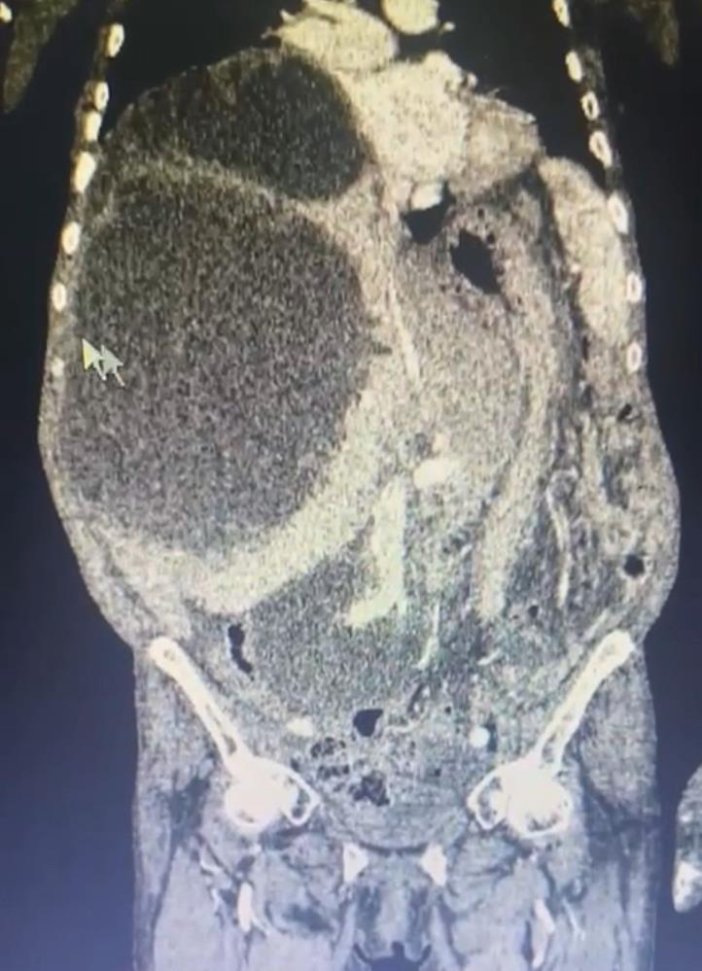

Kistlerin büyüklüğü dikkat çekerken Genel Cerrahi Uzmanı Opr. Dr. İsmet Çelik, dünya literatüründe tüm karnı dolduran ve 90 santime ulaşan kist görmediklerini belirterek Taşdelen'e yapılan gerekli tetkikler ve görüntüleme sonucu karaciğerinde üç adet kedi-köpek kisti (hidatik kist) tespit ettiklerini ifade etti.

Dünya literatüründe tüm karnı dolduran ve 90 santime ulaşan kist görmediklerini ifade eden Çelik, "Asiye Hanım, maalesef ihmal edilmiş bir hastamız. Bu kist, kedi ve köpeklerin dışkısı ve yediği yiyeceklerle bulaşan bir hastalık. Bu kist, genellikle tesadüfen yakalanabilir. Karaciğere yerleşir. Bu hastamızda da durum öyle olmuş. Ameliyat olamayacağı söylenip eve yollanmış. Bizler detaylandırıp ameliyat kararı aldık. Hastamızın karaciğerinde 3 ayrı kist vardı. Tüm karnı kist ile kaplıydı. 2 tanesinin tamamına çıkardık. Diğerini ise kontrolle alarak içini boşalttık. Dünya literatüründe tüm karnı dolduran ve 90 santime ulaşan kist görmedik. Ameliyatımız 2 saat sürdü. Hastamızın safra yolları kontrol edildi. Hastamızın durumu gayet iyi. Solunum cihazından bağımsız olarak kendi başına solunum yapabiliyor. En korktuğumuz şey; alerjik bir durumun olması. 90 santim çapındaki kist vücuda yayıldığı zaman alerjik bir durumda hastanın ölümüne sebep olabilmesi. Göremediğimiz yayılımlar için tedbir alıyoruz" diye konuştu.